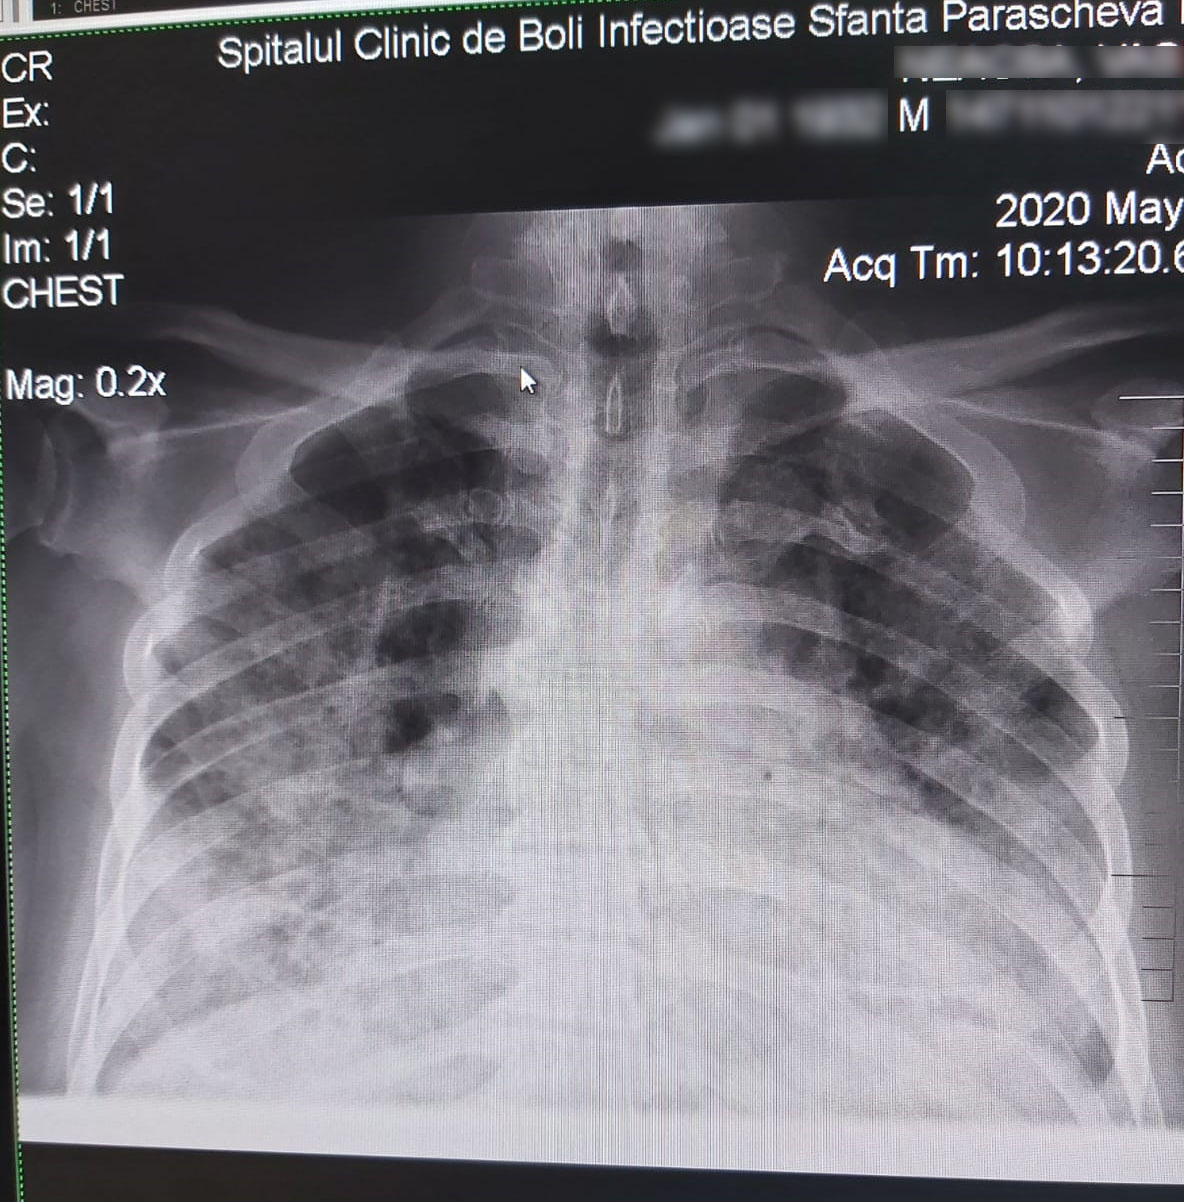

Puţini ştiu însă cum arată plămânii unei persoane infectate cu noul coronavirus. În imaginile pe care “Ziarul de Iaşi” vi le prezintă este vorba despre două cazuri extreme, ambele internate şi vindecate la Spitalul de Boli Infecţioase “Sfânta Parascheva”, scrie Ziarul de Iasi. Primul caz este al unui pacient tânăr, de 27 de ani, fără boli asociate şi cu o formă uşoară de boală, iar celălalt al unui pacient de 88 de ani, cu multiple comorbidităţi şi cu cinci-şase zile internare la Terapie Intensivă. “Când plămânul devine «alb», moartea poate surveni oricând, şi asta, în cazul SARS COV 2, se poate întâmpla şi de pe o zi pe alta”, a subliniat Carmen Dorobăţ, managerul Spitalului de Boli Infecţioase “Sfânta Parascheva”.

În cazul inflamaţiei provocate de SARS COV2, vorbim de o distrugere continuă a pereţilor alveolari, care poate merge până la sugrumarea sistemului. La nivelul plămânilor, virusul se îngroapă adânc în celule, unde se înmulţeşte foarte rapid. Apar acele pete albe pe radiografii. În cazul pacientului tânăr, de 27 de ani, fără comorbidităţi, se observă că aceste pete sunt puţine, fiind vorba de o formă uşoară de boală, care a necesitat atenţie, dar care nu a ridicat probleme nici la negativare şi nici la recuperare. Situaţia însă se schimbă radical atunci când e vorba de un pacient vârstnic, cu multiple comorbidităţi, printre care şi hipertensiune arterială, cum este a doua radiografie şi unde se vede că plămânii sunt afectaţi în proporţie 70%”, a declarat Carmen Dorobăţ, managerul Spitalului de Boli Infecţioase.